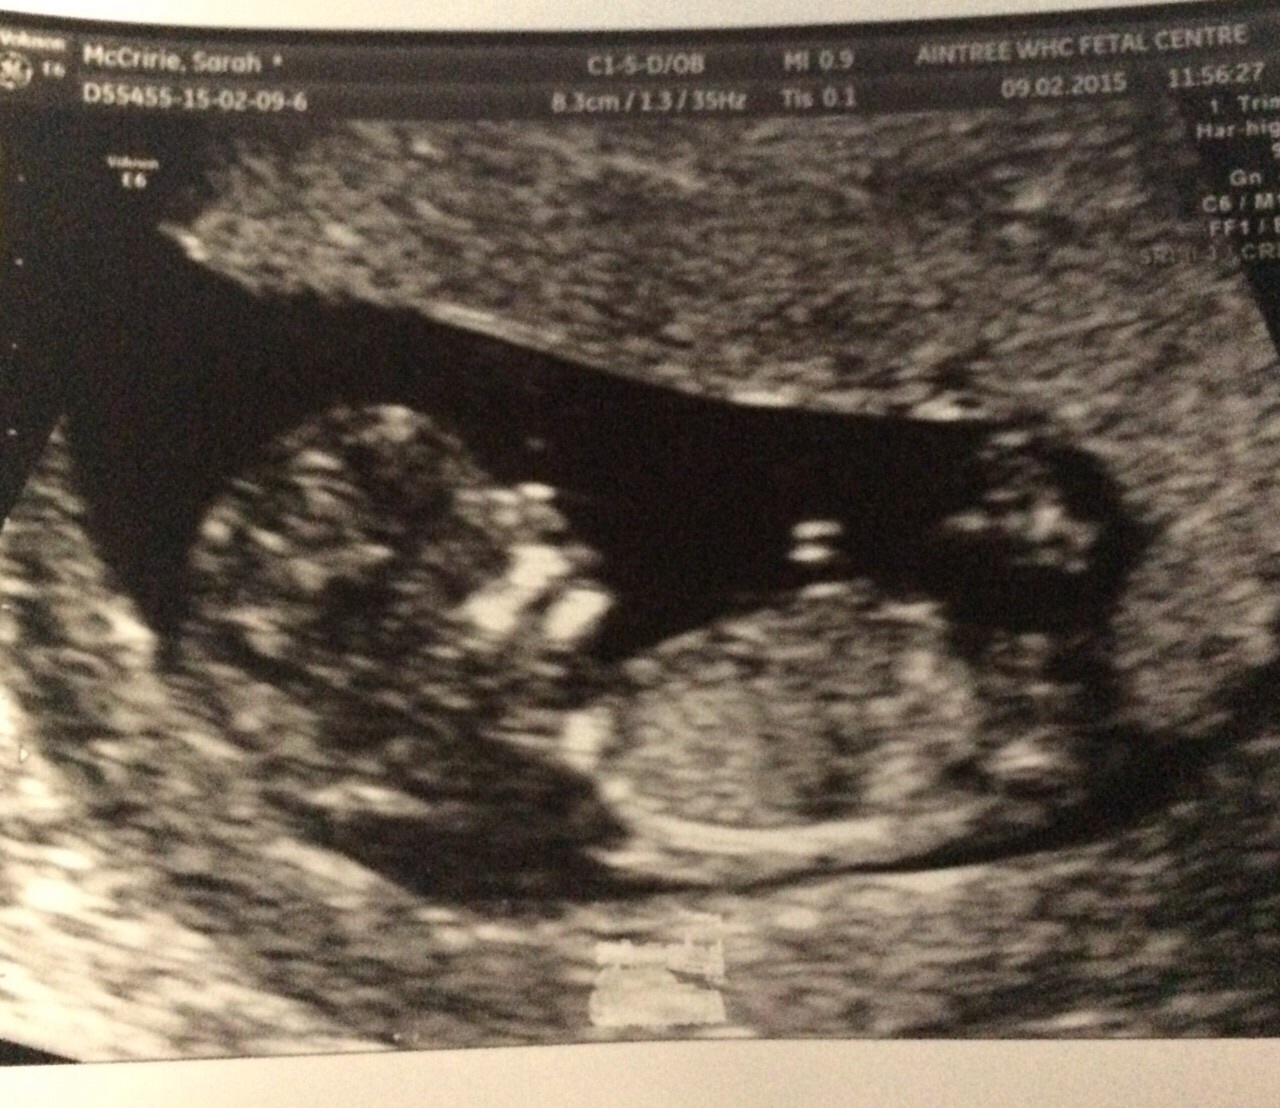

Is this a nub in this pic? If so what do you think girl or boy?